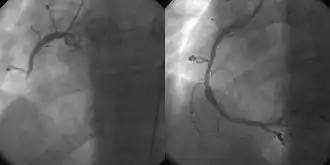

Angiografia coronária e angioplastia no infarto agudo do miocárdio (esquerda: Artéria Coronária Direita [ACD] fechada, direita: dilatada com sucesso)

As principais vantagens da utilização da abordagem de cardiologia intervencionista ou radiologia são evitar cicatrizes e dores e longa recuperação pós-operatória. Além disso, o procedimento de cardiologia intervencionista de angioplastia primária é agora o padrão ouro de tratamento para um infarto agudo do miocárdio. Envolve a extração de coágulos de artérias coronárias ocluídas e a implantação de stents e balões através de um pequeno orifício feito em uma artéria principal.[1][2]

o uso da angioplastia para o tratamento da obstrução das artérias coronárias em decorrência de doença arterial coronariana. Um cateter balão vazio é introduzido na artéria obstruída e insuflado para aliviar o estreitamento; certos dispositivos, como stents coronários, podem ser implantados para manter o vaso sanguíneo aberto. Vários outros procedimentos também podem ser realizados ao mesmo tempo. Após um infarto, pode ser restrito ao vaso culpado (aquele cuja obstrução ou trombose é suspeita de causar o evento) ou revascularização completa; a revascularização completa é mais eficaz em termos de eventos cardíacos adversos maiores e mortalidade por todas as causas.[4]